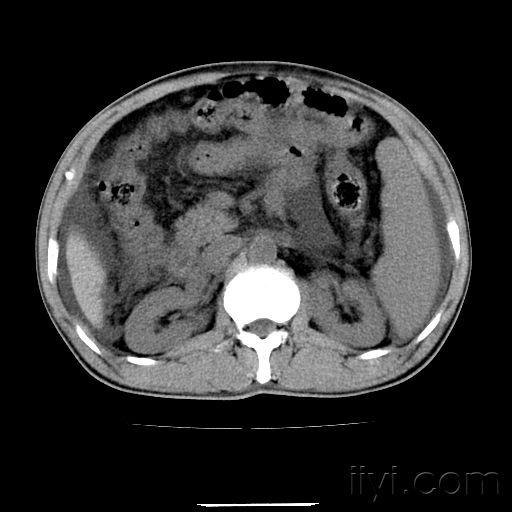

腹部CT平扫

急查腹部ct可见胰腺体积增大,密度减低,轮廓模糊,周围斑片状渗出.